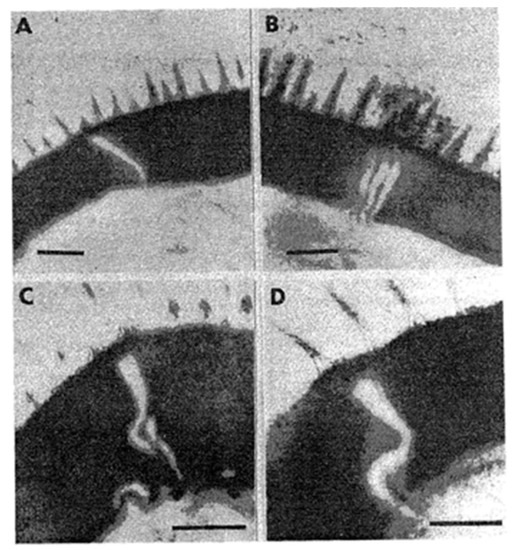

- Ždárská, Z.; Giboda, M.; Zenka, J. The ultrastructure of Schistosoma mansoni egg: The line of hatching. Helminthologia 1992, 29, 63–65. [Google Scholar]